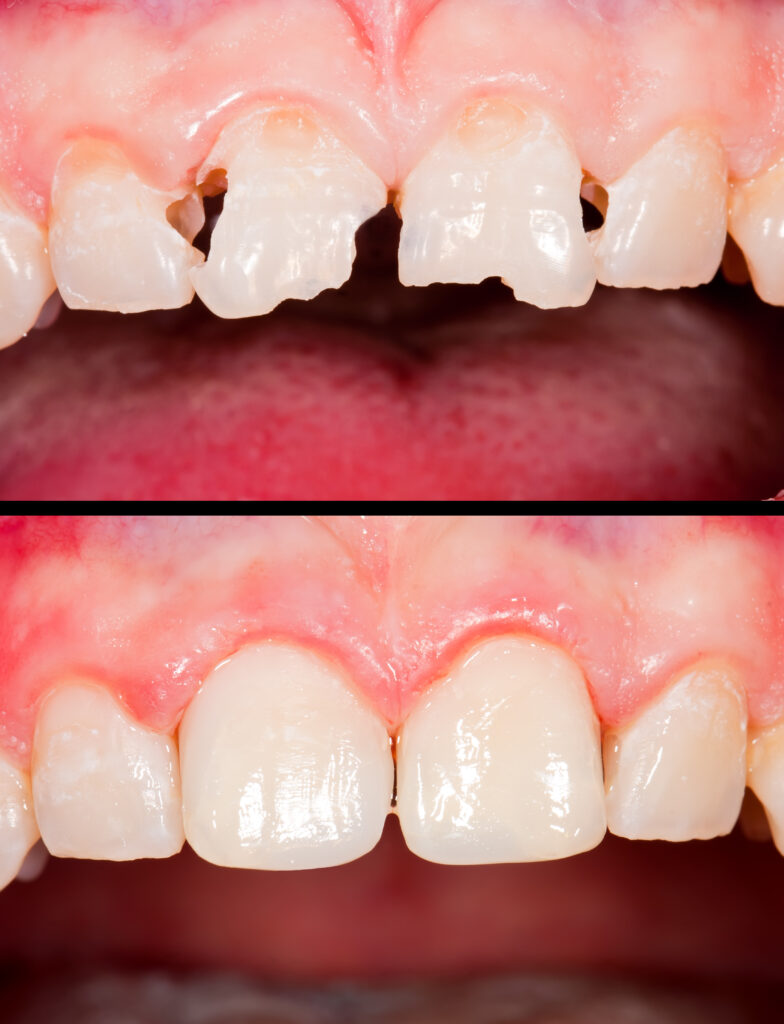

Crowns and Bridges

Restore Strength. Rebuild Your Smile. Regain Confidence.

Damaged or missing teeth can affect more than just your appearance — they can impact how you eat, speak, and feel about your smile. At Plaza Dental Care, we provide high-quality dental crowns and bridges designed to restore both function and aesthetics.

What is Dental Crown?

A dental crown is a custom-made “cap” placed over a damaged or weakened tooth to restore its shape, size, strength, and appearance.